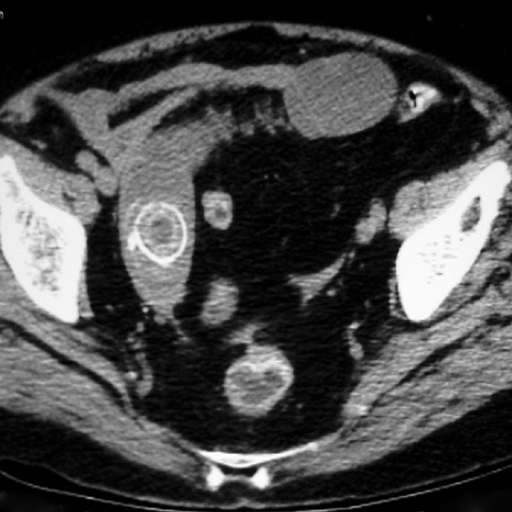

Patient hospitalisée pour douleurs en FIG, fièvre. qu’est ce que c’est?

Diverticulite aiguë sigmoïdienne